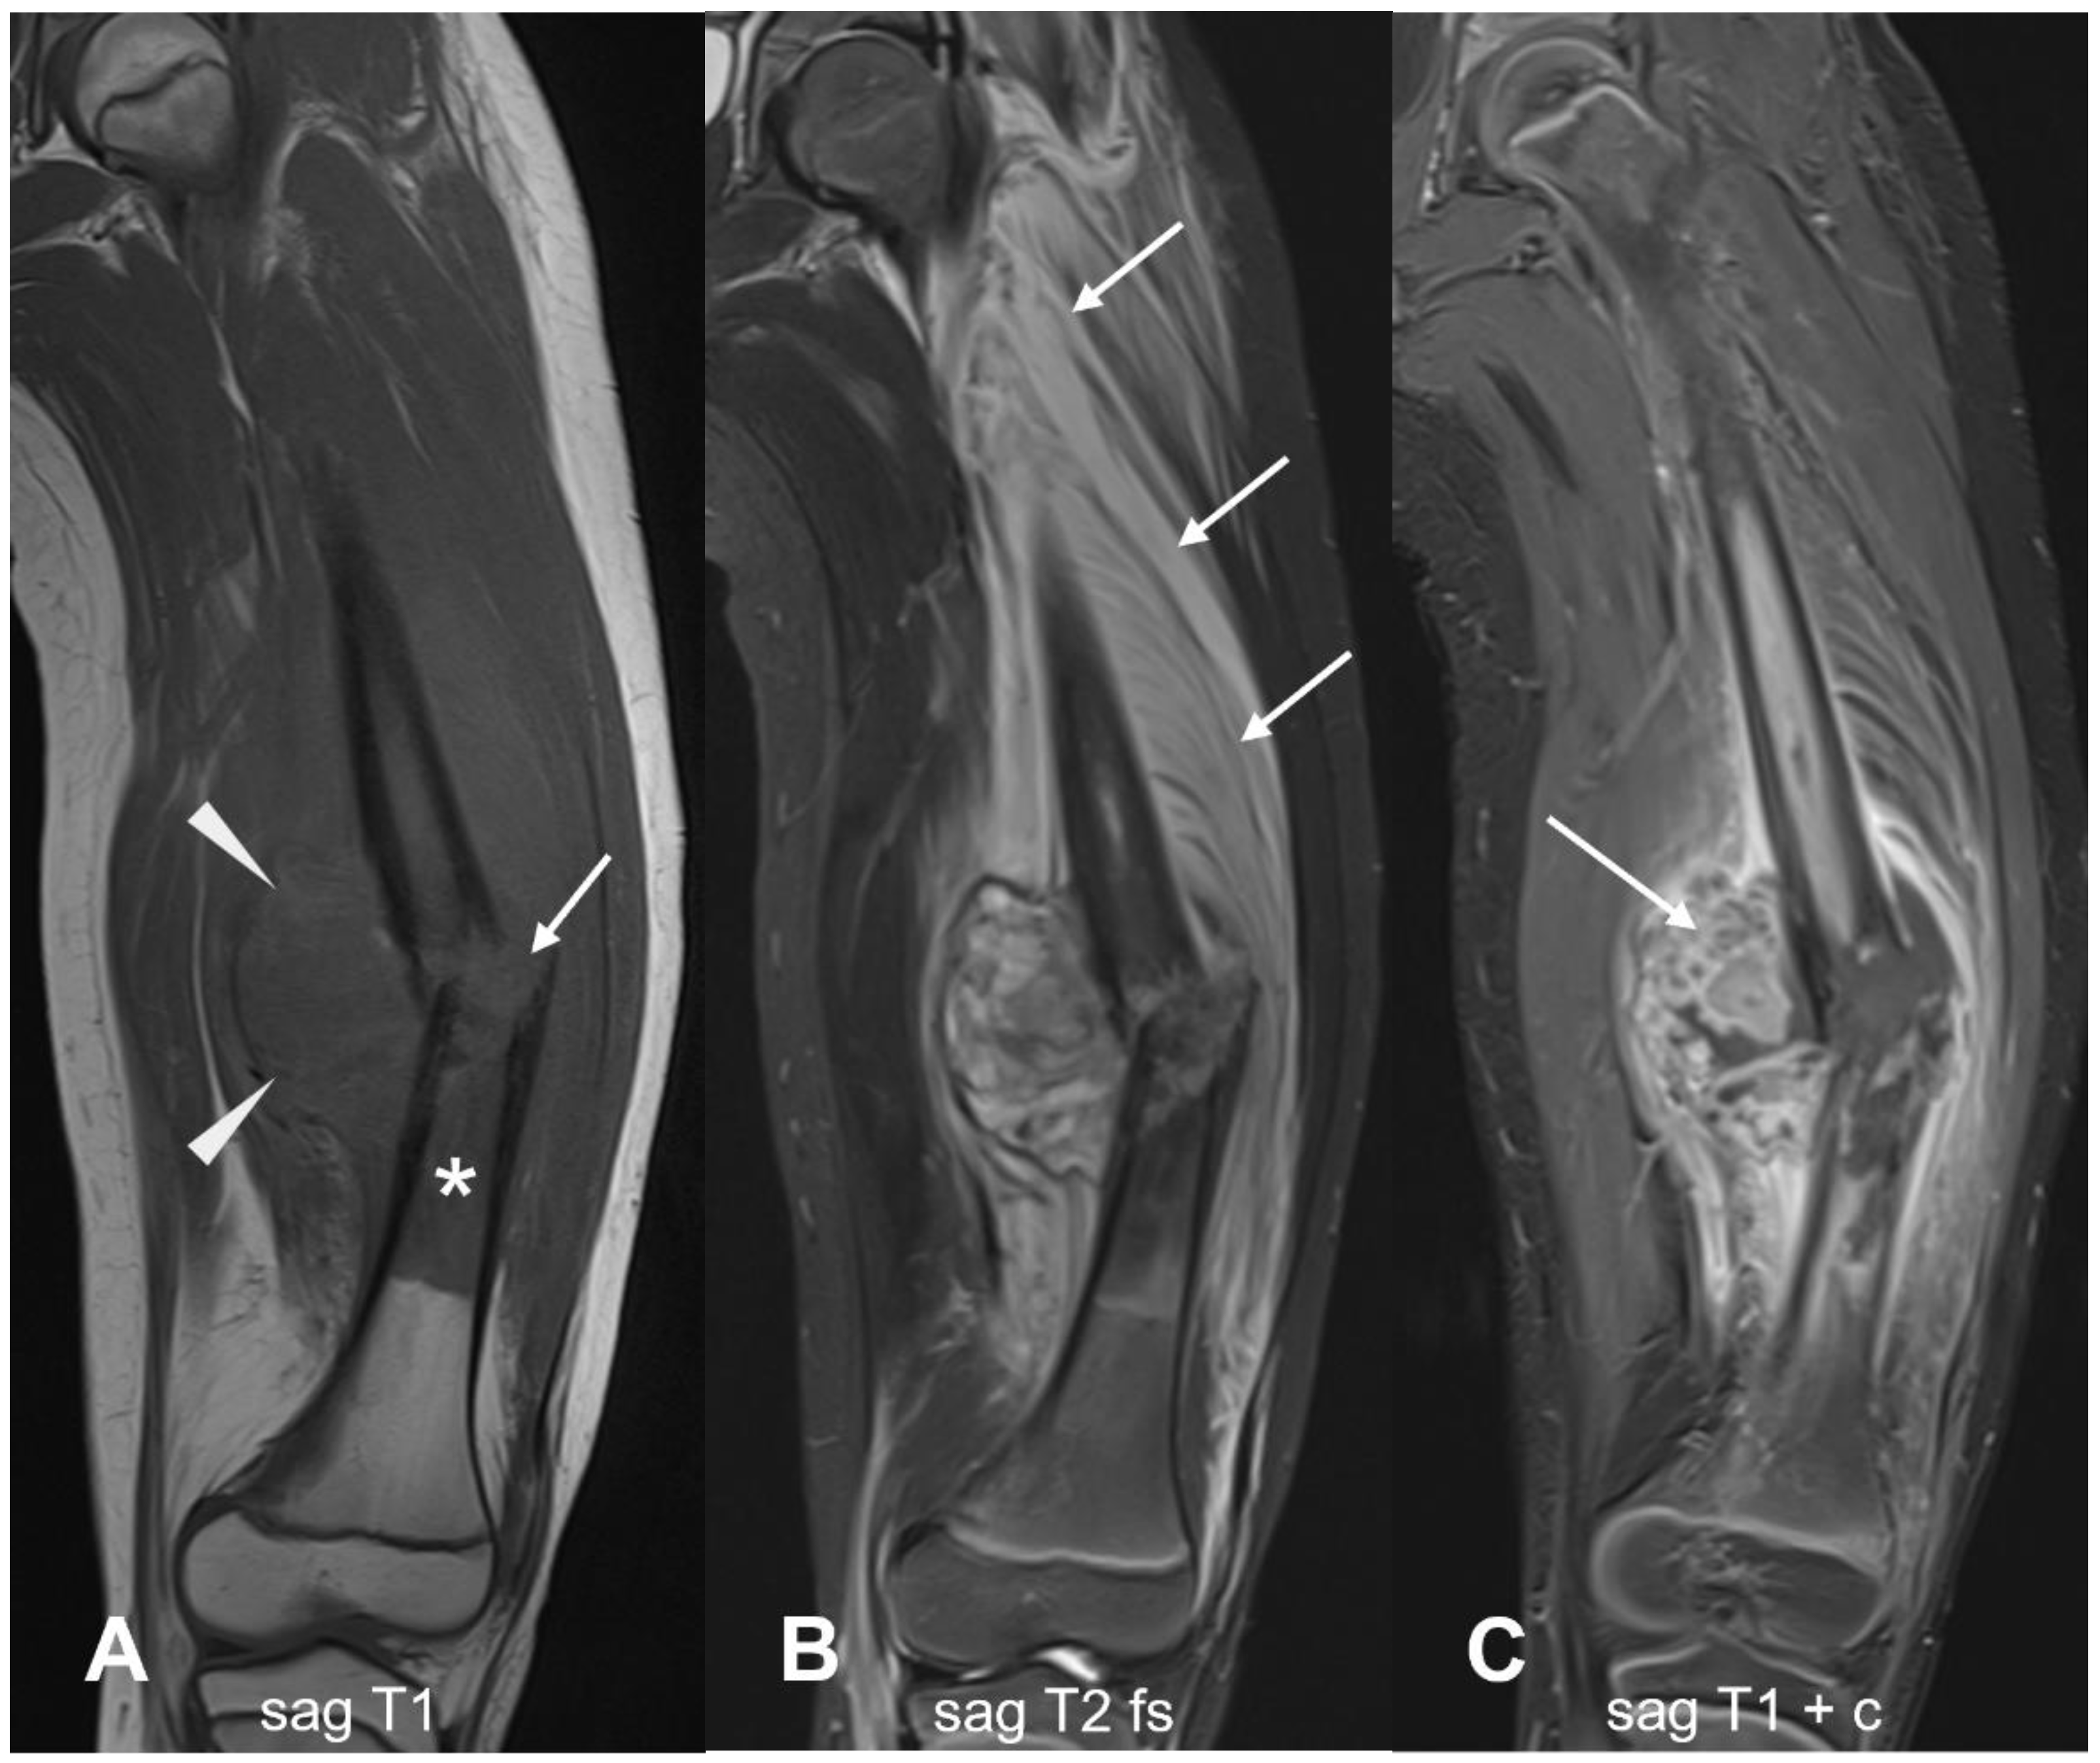

3.1.1. Conventional Osteosarcoma

3.1.5. Low-Grade Central Osteosarcoma